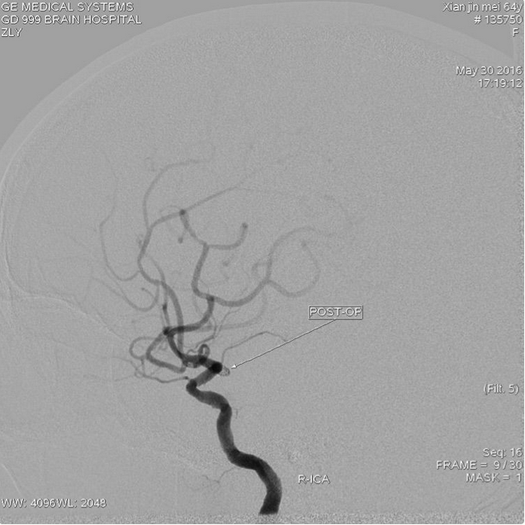

栓塞后动脉瘤不显影,瘤颈口与动脉开口处稍残留,小脑后下动脉显影通畅

Livs(212517)支架辅助栓塞后交通动脉瘤,动脉瘤不显影